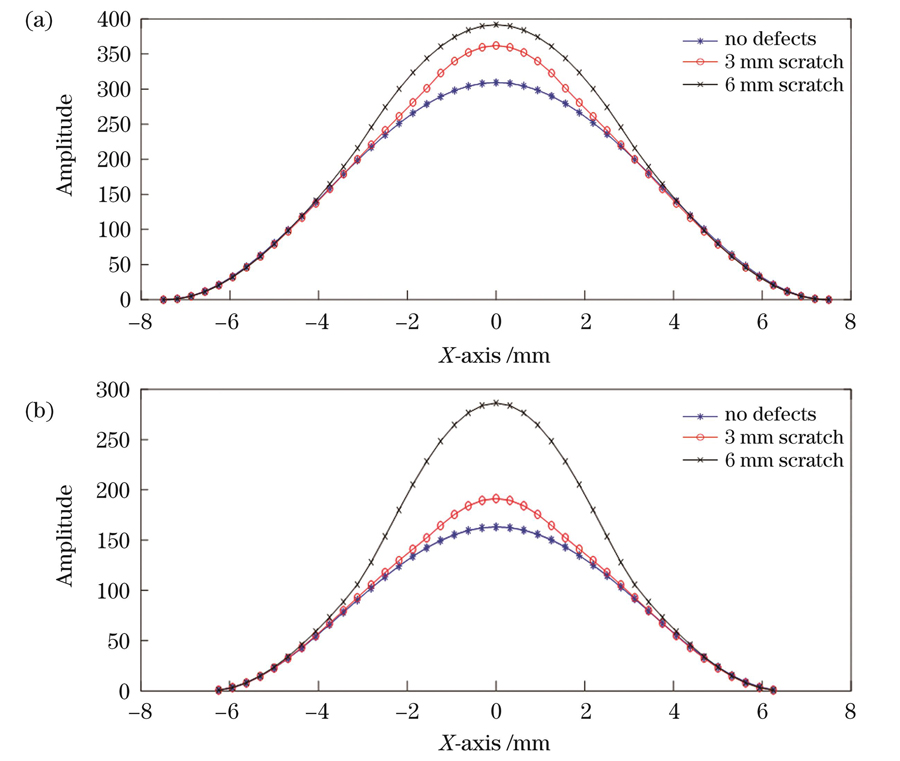

图 6. 划伤薄膜振幅分布截面图。(a)中心划伤薄膜y=0.1处;(b)偏心划伤薄膜y=-3.7处

Fig. 6. Section of amplitude of scratched films. (a) Section at y=0.1 of the centrally scratched film; (b) section at y=-3.7 of the eccentrically scratched film

针对上述的薄膜划伤仿真分析,同样进行了相应的实验验证,得到的中心划痕样本的一阶振动模态图如